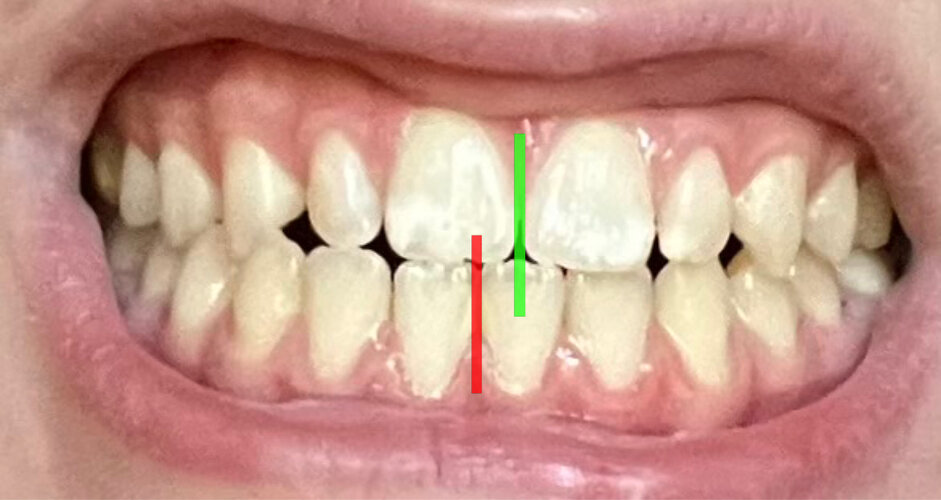

Let me explain first i am 14 years old and my teeth are fucked, they're straight, only my bite is completely misaligned. On top of this i have a slight underbite making my chin projection to look better. What should i do?

it’s over for me. Maxilla was already slightly recessed tho so